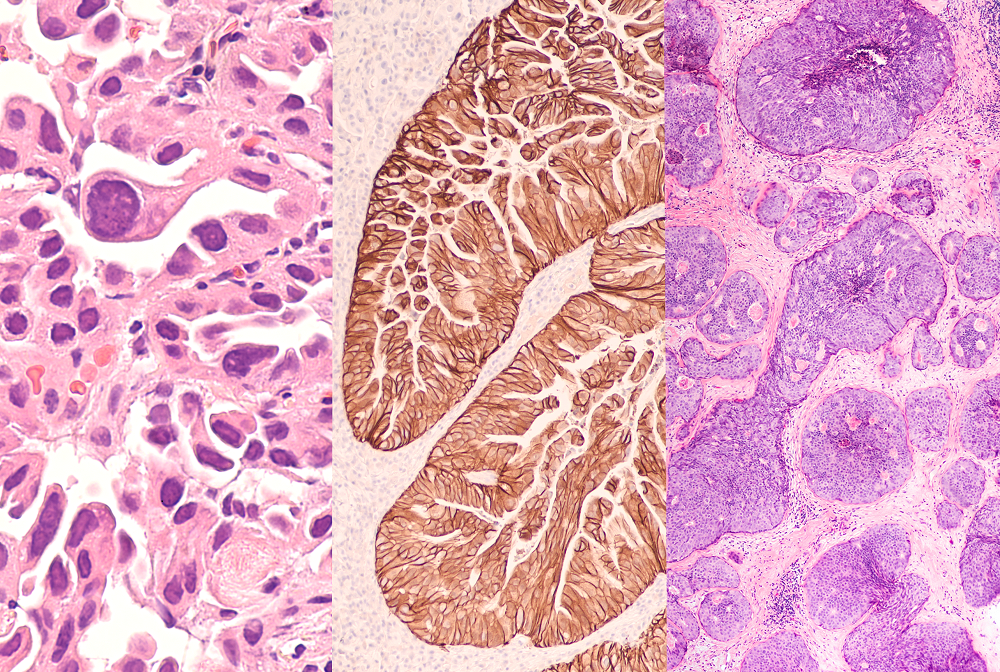

The study, published May 1 in Cancer Discovery, shows that the B-cell lymphoma 6 (BCL6) gene helps cancer cells overcome the DNA damage caused by chemotherapy, radiation or other cancer therapies. This defense mechanism originally evolved to help protect vertebrates’ ancient relatives survive harsh conditions, but it springs into action in cancer cells stressed by rapid growth and treatment. Blocking this defense mechanism in cancer cells in the lab makes them more susceptible to cancer treatments, the study also showed.

BCL6 is very active in blood cancers because the gene helps immune cells in the blood called B-cells produce antibodies—a process that can generate stress and DNA damage. But it wasn’t clear to researchers why BCL6 was also being found in cancers like lung, stomach and triple negative breast cancers. Or why patients with more BCL6 had worse outcomes.